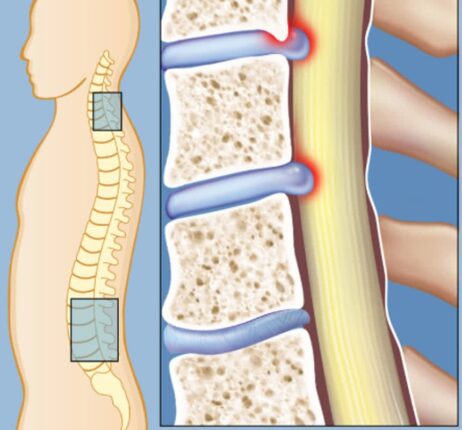

척추관 협착증 수술 증상 치료 5가지, 그 외에도 회복 재활을 위한 방법 공유